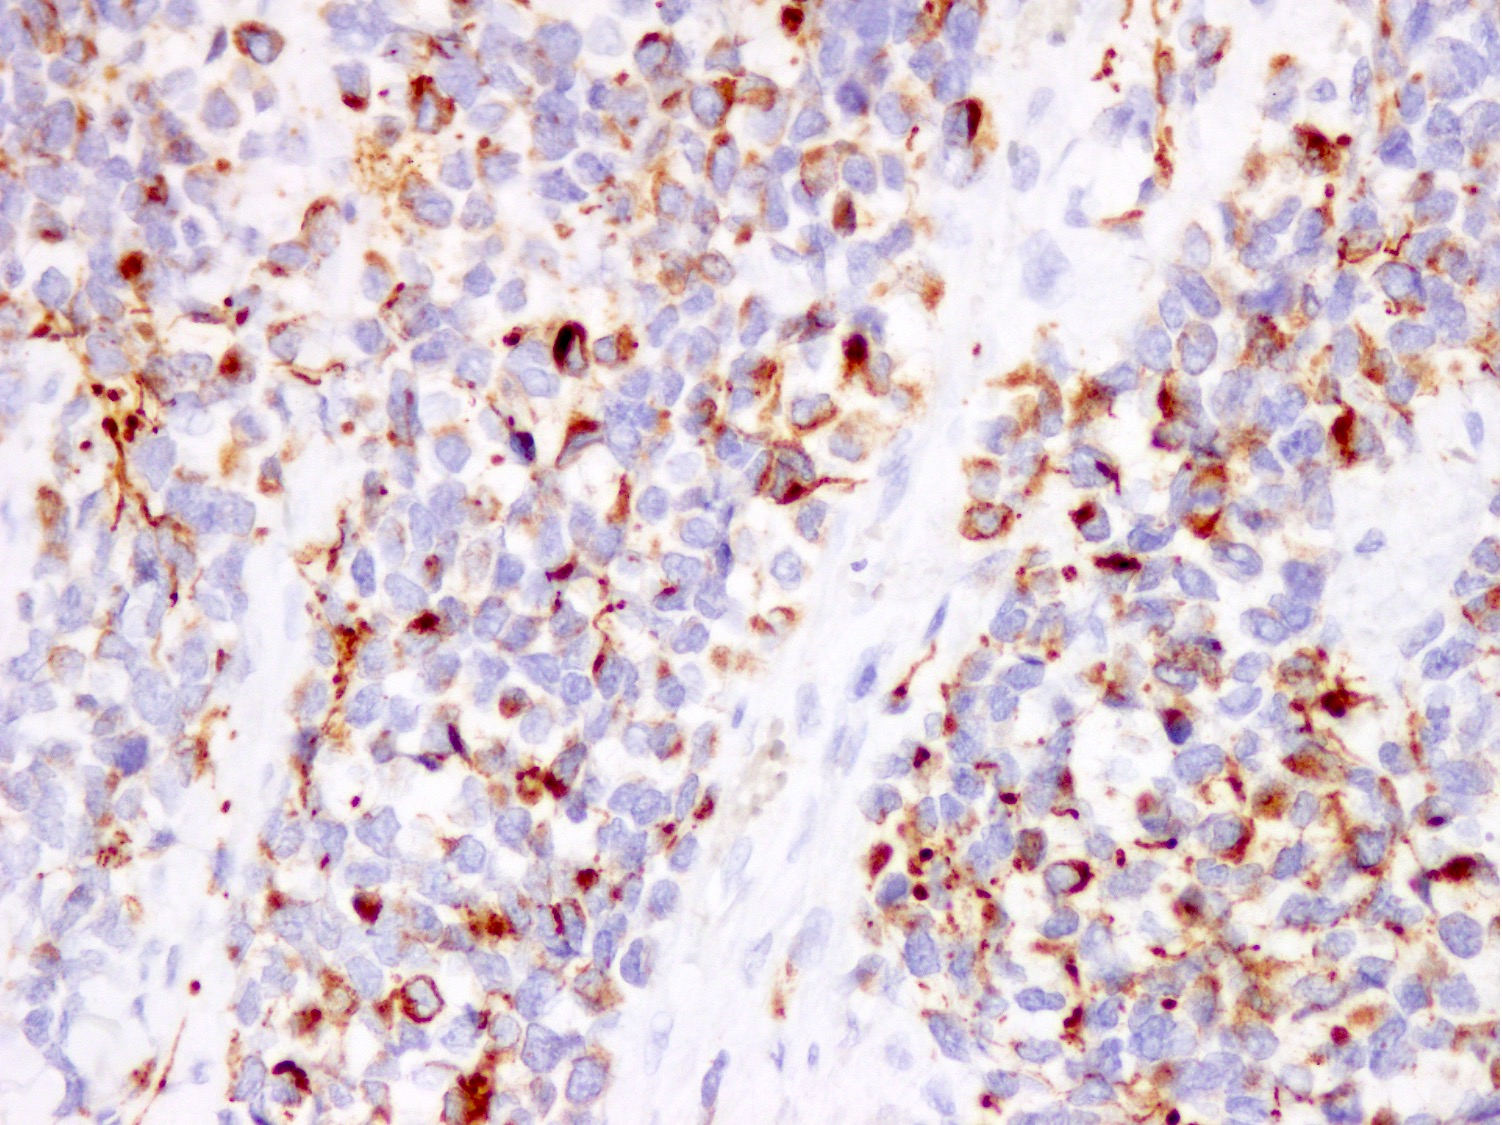

Microscopic (histologic) images

Contributed by Nasir Ud Din, M.B.B.S.

Positive stains

- Stains for myogenic differentiation:

- Desmin

- MyoD1 (variable)

Negative stains